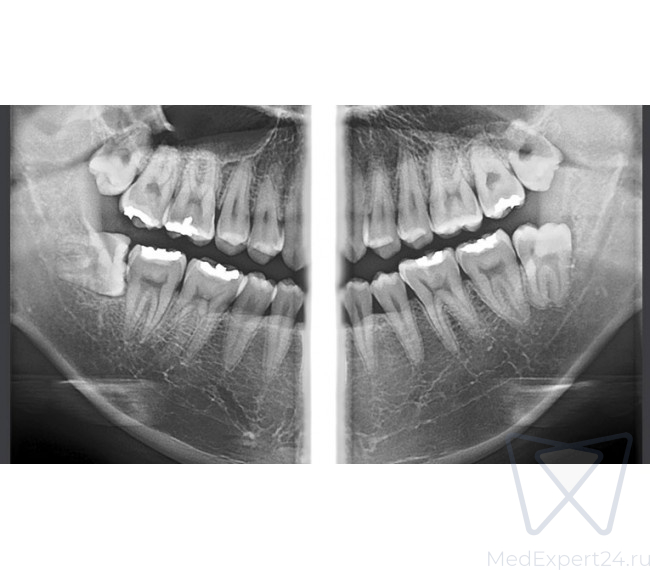

- Четкие изображения с помощью технологии MAR (Metal Artifact Reduction) – алгоритм уменьшения влияния артефактов, возникающих от металлов в челюсти. Уменьшает эффект отражения рентгеновских лучей от объектов с высокой плотностью и позволяет улучшить диагностику вокруг этих объектов.

- Четкие изображения с помощью технологии AMF (Adaptive Moving Focus) – адаптивное смещение фокуса, для получения качественного панорамного снимка и оптимизации соотношения сигнал/шум

Сниженная доза облучения и технология расширенной обработки изображений Наши алгоритмы расширенной обработки изобра- жений позволяют удалить помехи с изображения и выделяют края при меньшей дозе облучения и со- кращенном времени экспозиции. Оптимизирован- ные педиатрические обследования в дальнейшем позволят снизить лучевую нагрузку с сохранением качества изображения при лечении детей.

- Стандартная панорамная

- Ортозональная панорамная

- Ортогональная панорамная